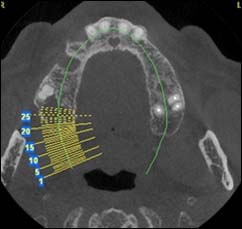

EXAMENS TOMOGRAPHIES VOLUMIQUES TYPE SCANNER OU CÔNE BEAM :

Dernière technologie à notre disposition, cette technique permet de voir en 3 dimensions des images de votre bouche et de mettre en évidence des pathologies ou des anomalies que les autres techniques ne permettent pas d’objectiver.

Coupe axiale

Reconstruction panoramique

Reconstruction coronale